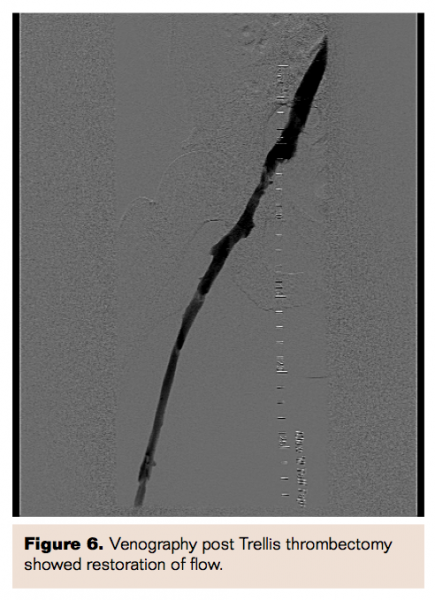

Three weeks later, she was brought back to the cardiac catheterization laboratory for venography and for possible removal of the IVC filters. Venography revealed re-occlusion of the left iliac system secondary to thrombus. A decision was made to proceed with balloon angioplasty of the left iliac system. After multiple balloon dilatations, intravascular ultrasound (IVUS) was performed, which revealed compression of the left iliac vein by the right iliac artery. Two self-expanding 12 mm x 60 mm and 10 mm x 60 mm Protégé GPS self-expanding stents (Covidien Inc) were then deployed into the left common iliac venous system. There was excellent flow through the stents via both wide-open bilateral IVC and pelvic connectors. We chose not to remove the IVC filters at this juncture because of the presence of extensive clot burden. The pelvic connector between left IVC and right iliac vein was noted to be behind the aortoiliac bifurcation and was compressed. IVUS of the pelvic connector was performed, which confirmed the suspicion of compression. After performing balloon dilatation of the compression, a 12 mm x 40 mm Protégé GPS self-expanding stent was deployed which subsequently showed excellent flow in the connector and in bilateral IVC.

Two weeks later, she underwent venous Doppler, which revealed normal flow in bilateral IVC, the iliac veins and bilateral lower extremity. She also underwent repeat venography, which confirmed patent stents with good blood flow through the left iliac system and no recurrence of thrombus formation. Both IVC filters were removed. She was continued on warfarin anticoagulation and was followed up in an outpatient clinic after 1 month without recurrence of symptoms.